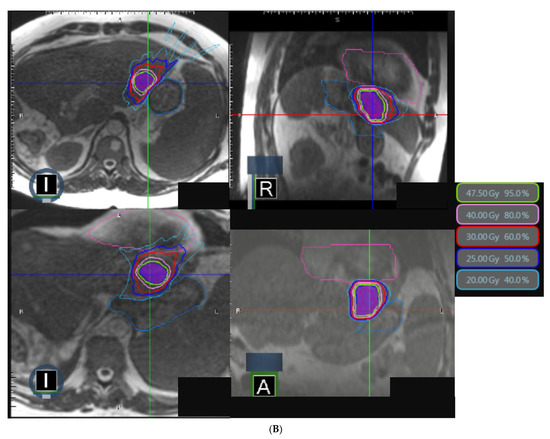

Stereotactic MR-Guided Radiotherapy for Liver Metastases: First Results of the Montpellier Prospective Registry Study

by Karl Bordeau, Morgan Michalet, Aïcha Keskes, Simon Valdenaire, Pierre Debuire, Marie Cantaloube, Morgane Cabaillé, William Jacot, Roxana Draghici, Sylvain Demontoy, Xavier Quantin, Marc Ychou, Eric Assenat, Thibault Mazard, Ludovic Gauthier, Marie Dupuy, Boris Guiu, Céline Bourgier, Norbert Aillères, Pascal Fenoglietto, David Azria and Olivier Riouadd Show full author list remove Hide full author list

J. Clin. Med. 2023, 12(3), 1183; https://doi.org/10.3390/jcm12031183 - 2 Feb 2023

Liver stereotactic body radiotherapy (SBRT) is a local treatment that provides good local control and low toxicity. We present the first clinical results from our prospective registry of stereotactic MR-guided radiotherapy (MRgRT) for liver metastases. All patients treated for liver metastases were included [...] Read more.

Liver stereotactic body radiotherapy (SBRT) is a local treatment that provides good local control and low toxicity. We present the first clinical results from our prospective registry of stereotactic MR-guided radiotherapy (MRgRT) for liver metastases. All patients treated for liver metastases were included in this prospective registry study. Stereotactic MRgRT indication was confirmed by multidisciplinary specialized tumor boards. The primary endpoints were acute and late toxicities. The secondary endpoints were survival outcomes (local control, overall survival (OS), disease-free survival, intrahepatic relapse-free survival). Twenty-six consecutive patients were treated for thirty-one liver metastases between October 2019 and April 2022. The median prescribed dose was 50 Gy (40–60) in 5 fractions. No severe acute MRgRT-related toxicity was noted. Acute and late gastrointestinal and liver toxicities were low and mostly unrelated to MRgRT. Only 5 lesions (16.1%) required daily adaptation because of the proximity of organs at risk (OAR). With a median follow-up time of 17.3 months since MRgRT completion, the median OS, 1-year OS and 2-year OS rates were 21.7 months, 83.1% (95% CI: 55.3–94.4%) and 41.6% (95% CI: 13.5–68.1%), respectively, from MRgRT completion. The local control at 6 months, 1 year and 2 years was 90.9% (95% CI: 68.3–97.7%). To our knowledge, we report the largest series of stereotactic MRgRT for liver metastases. The treatment was well-tolerated and achieved a high LC rate. Distant relapse remains a challenge in this population. Full article